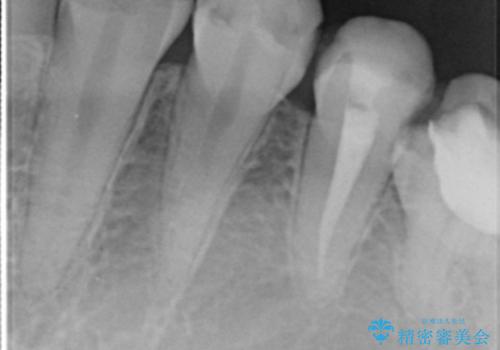

精査したところ、ほとんどの歯が保険内のレジンで充填されており、咬み合わせも悪く咬合していない歯もありました。

虫歯をしっかりと治療したのち、オールセラミッククラウンによる補綴治療を行いました。

下顎の埋伏していた親知らずも抜去しました。